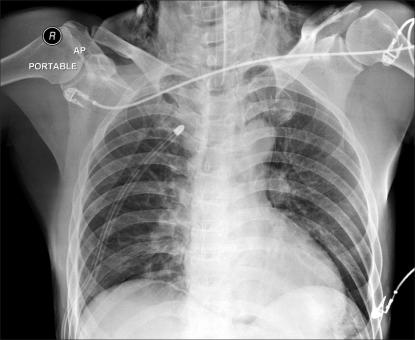

We experienced an extremely rare complication during performance of laparoscopic totally extraperitoneal (TEP) inguinal hernia repair for a 57-year-old healthy man. About 50 minutes after CO(2) insufflation, the patient developed tachycardia, hypoxemia, hypercapnia and an increased airway pressure. Right pneumothorax with subcutaneous emphysema was recognized on the emergency chest X-ray and this was successfully treated by chest tube insertion. Anesthesiologists should be aware of the possible occurrence of pneumothorax during laparoscopic TEP hernia repair.

我们在为一名 57 岁健康男性行腹腔镜完全腹膜外(TEP)腹股沟疝修补术中遇到了一种极其罕见的并发症。在二氧化碳充气约 50 分钟后,患者出现心动过速、低氧血症、高碳酸血症和气道压力升高。急诊胸片显示右侧气胸伴皮下气肿,经胸腔引流管插入成功治疗。麻醉师应意识到在腹腔镜 TEP 疝修补术中可能发生气胸。